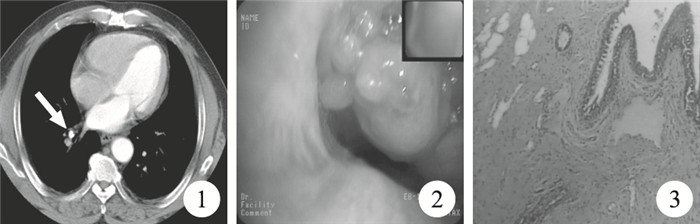

臨床資料??患者,男,67歲。因胸悶伴咳嗽1月余入院。既往體健,無吸煙史。查體:淺表淋巴結未腫大,氣管居中,右下肺呼吸音稍低,未聞及明顯的干濕性啰音。胸部CT示:右下肺條索高密度影(圖 1),伴有部分肺不張可能。纖維支氣管鏡示:右肺下葉基底段支氣管開口有新生物(圖 2),右肺下葉背段開口外壓性狹窄,病理活檢為支氣管黏膜慢性炎癥。入院診斷:右肺下葉不張,肺癌?入院后復查胸部增強CT示:右下肺少許炎癥,基底段管腔內可見新生物。在我科行右肺下葉切除術,切除的標本可見距支氣管切端1 cm處支氣管腔內見一灰白色腫塊,大小1.2 cm×0.8 cm×0.5 cm,切面灰白,質硬,常規病理檢查提示右肺下葉錯構瘤伴骨化(圖 3)。術后患者恢復良好出院,隨訪1年,未見腫瘤復發。